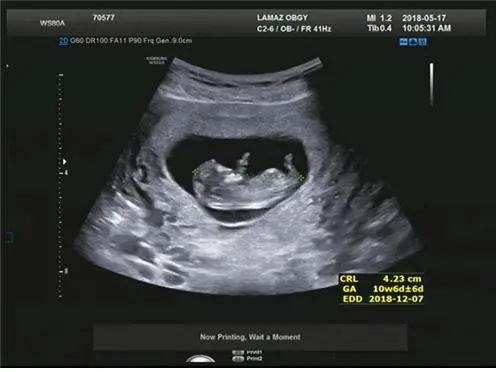

그렇게 말하고 우리는 뱃속 아이를 보러 갔다. 6주 차에 임신 확인을 하고 중간에 한 번 더 병원에 왔어야 했는데 넷째 엄마의 여유를 부렸다. 한 달 만에 찾은 병원이다. 임신 10주 차가 되었다. 침대에 누워 초음파로 배를 보기 시작했다. 남편과 나는 눈이 휘둥그레지고 말았다. 눈 코 입 팔다리가 다 생겨있었다. 4.3Cm라는 작은 생명체 안에 필요한 부분들이 다 만들어져 가고 있었다. 겨우 10주 만에 일어난 일이다. 이 작은 생명체 안에 말이다. 새삼 생명 탄생의 경이로움마저 느껴졌다.

10주 차 아가 모습

남편과 나는 이 아이가 우리가 생애 처음 만나는 아이처럼 호들갑을 떨며 좋아했다.